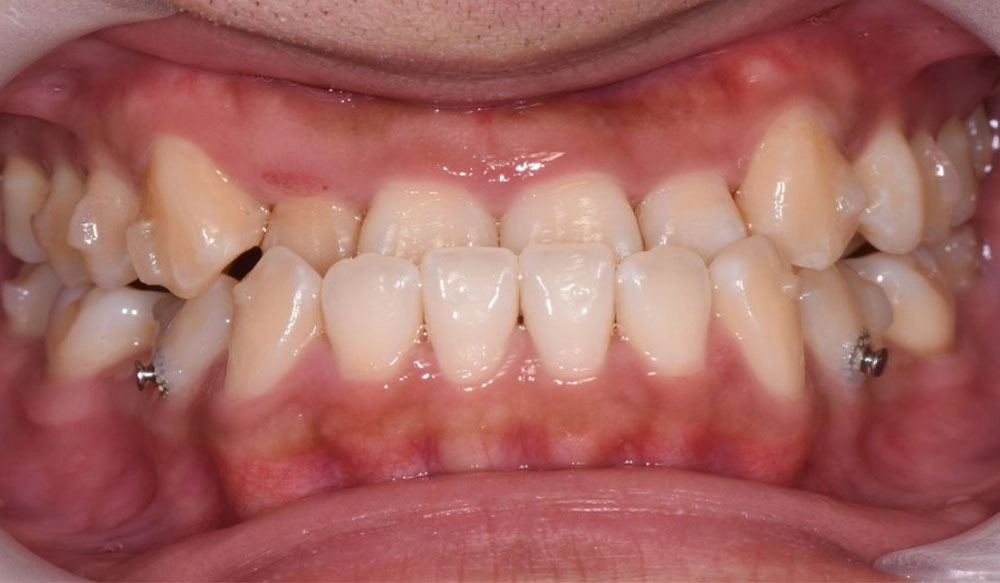

Mandibular Advancement

Invisalign® treatment with mandibular advancement is aimed for growing patients presenting with retrognathic Class II malocclusions in permanent dentition or stable late mixed dentition. The special feature of precision wings are integrated into the Invisalign aligners.

Patient Information:

Age: 14

Gender: male

Invisalign Treatment Option: Invisalign Teen with MA

Total Treatment Time:

36 months